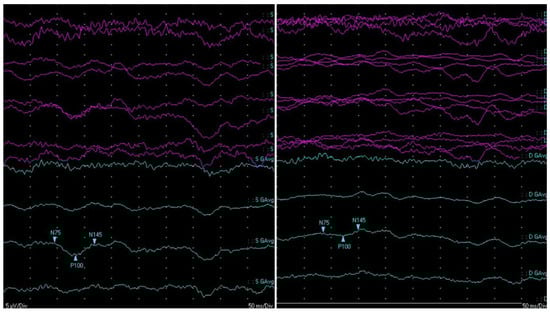

The first cerebral ischemic event manifested as left hemiparesis that occurred one year later (in 2018). No recognizable etiology of the ischemic stroke was found, and an insertable cardiac monitoring device was implanted. Starting two years after this first cerebral event, the patient slowly developed a progressive decrease in visual acuity and severe physical and cognitive deterioration. He underwent multiple brain magnetic resonance images (MRIs), which showed an accumulation of (sub)acute lacunar brain infarction, i.e., small (<20 mm in diameter) ischemic lesions that affect the CNS white and grey matter, as well as diffuse brain and optic nerve atrophy (Figure 2). Several serological screening tests for common infections, rheumatologic/systemic vasculitis, and inherited or acquired coagulation disorders were negative over time, except for an isolated lupus anticoagulant (LAC) positivity, which was not confirmed after at least 12 weeks. Carotid and transcranial doppler ultrasounds, MR angiography, and cardiac electronic devices–remote interrogations were steadily unremarkable. During the hospitalization at our clinic in 2022, CSF analysis showed an increased level of protein (71.3 mg/dL-n.v.: 15.0–45.0 mg/dL) and intrathecal oligoclonal bands (OCBs), together with its analogous presence in the peripheral blood (pattern type 4—“mirror”). Neither leukocytes nor red blood cells nor increased lactate levels were present in the CSF. Testing for antibodies for paraneoplastic syndrome was negative. At the same time, the CSF multiplex–polymerase chain reaction assay ruled out neuroinfectious diseases, and CNS intravascular neoplasms appeared unlikely since radiological evaluation, CSF cytopathology and flow cytofluorimetry were both negative, and the disease course was not rapidly progressive. Visually evoked potentials (VEPs) showed bilateral abnormalities, which were worse on the right side, mainly due to axonal damage (Figure 3), and a fundoscopic inspection did not demonstrate pathologic findings. Optical coherence tomography and fundus fluorescein angiography were not performed. No strategic infarct at the visual cortex was evident on brain MRI. Nerve conduction studies showed normal conduction velocities, latency, and amplitudes in the limbs’ main motor and sensory nerves; a needle electromyography was within limits.

Figure 3. Visual conduction pathway assessment. The reversal pattern of VEP showed a predominant reduction in the amplitude of P100 in both eyes (worse on the right panel—right eye), which was not associated with a substantial modification of latency.